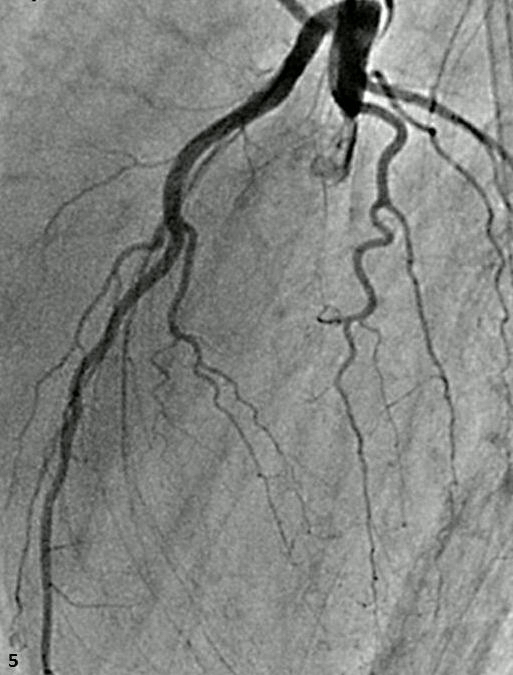

Abstract PDF ECG 1 Angio 1 Angio 2 Angio 3 Angio 4 ECG 2 Table Chart Original File 1 2 3 4 5 6 Reply to reviewer Fig. 1. ECG during myocardial infarction Fig. 2. Coronary angiography of LCA during myocardial infarction Fig. 3. Coronary angiography of LCA during myocardial infarction Fig. 3a. Coronary angiography of LCA during myocardial infarction Fig. 4. Coronary angiography of LCA 2 years after myocardial infarction Fig. 5. Coronary angiography of LCA 2 years after myocardial infarction Fig. 6. ECG 2 years after myocardial infarction Fig. 7. Thrombolytic trials in patients with coronary artery dissection Fig. 8. Flow chart of the study selection process -